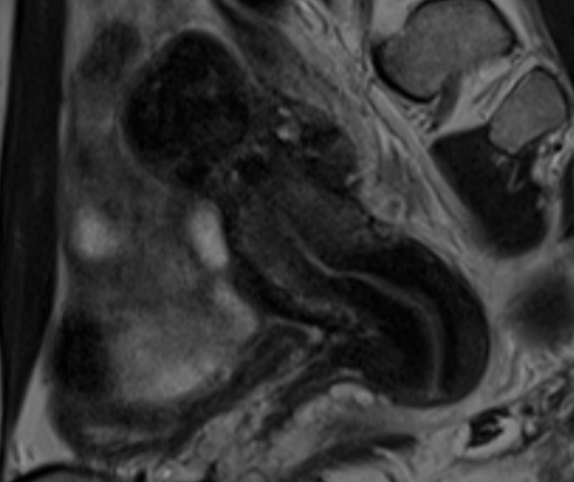

. Ressonància magnètica (RM).

És un examen que utilitza un camp magnètic i ones de ràdio per crear imatges detallades dels òrgans i teixits dins del cos. Una ressonància magnètica permet la planificació quirúrgica. Proporciona informació detallada al cirurgià sobre el lloc i la mida dels implants.

- endometriosis en Resonància

- endometrioma a la ressonància

- ressonància magnètica